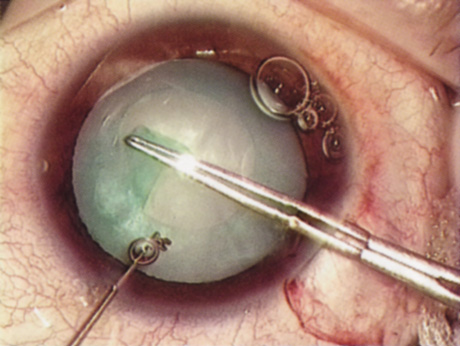

ANTERIOR CAPSULOTOMY

One of the most beneficial techniques developed over the last decade is capsulorrhexis. A continuous curvilinear anterior capsular opening helps prevent intraoperative and postoperative complications. With capsulorrhexis, mechanical strength of the capsular opening is superior to that in a can-opener capsulotomy; thus, a tear to the posterior capsule with subsequent vitreous loss is much less likely.96 Capsulorrhexis allows for nuclear manipulation with less risk of posterior capsule rupture. Cortex removal is made easier as well, because it becomes easier to differentiate cortical material from anterior capsule. Should a posterior capsular tear occur, sulcus fixation is more likely attainable with the presence of a clearly visible residual anterior capsular rim. Placement of both IOL haptics into the capsular bag is more certain with capsulorrhexis because the surgeon can more easily visualize the haptics gliding beneath the anterior capsular rim.

Capsulorrhexis can be performed with a cystitome, capsulorrhexis forceps, or combination-type instruments. Regardless of which instrument is used, several principles can help the surgeon successfully complete capsulorrhexis. It is important to maintain the anterior chamber, because making the chamber shallow increases tension on the zonules and causes the tear to run peripherally. The authors recommend the use of a viscoelastic agent for maintaining chamber depth and, of course, for endothelial protection. Therefore, if the tear begins to run peripherally, the surgeon should redeepen the anterior chamber before attempting to redirect the tear. Additionally, folding the capsule margin can aid the surgeon in redirecting the tear more accurately (Fig. 10).

Fig. 10. The capsulorrhexis tear is more easily redirected by folding the capsule over, in advance of the tear.